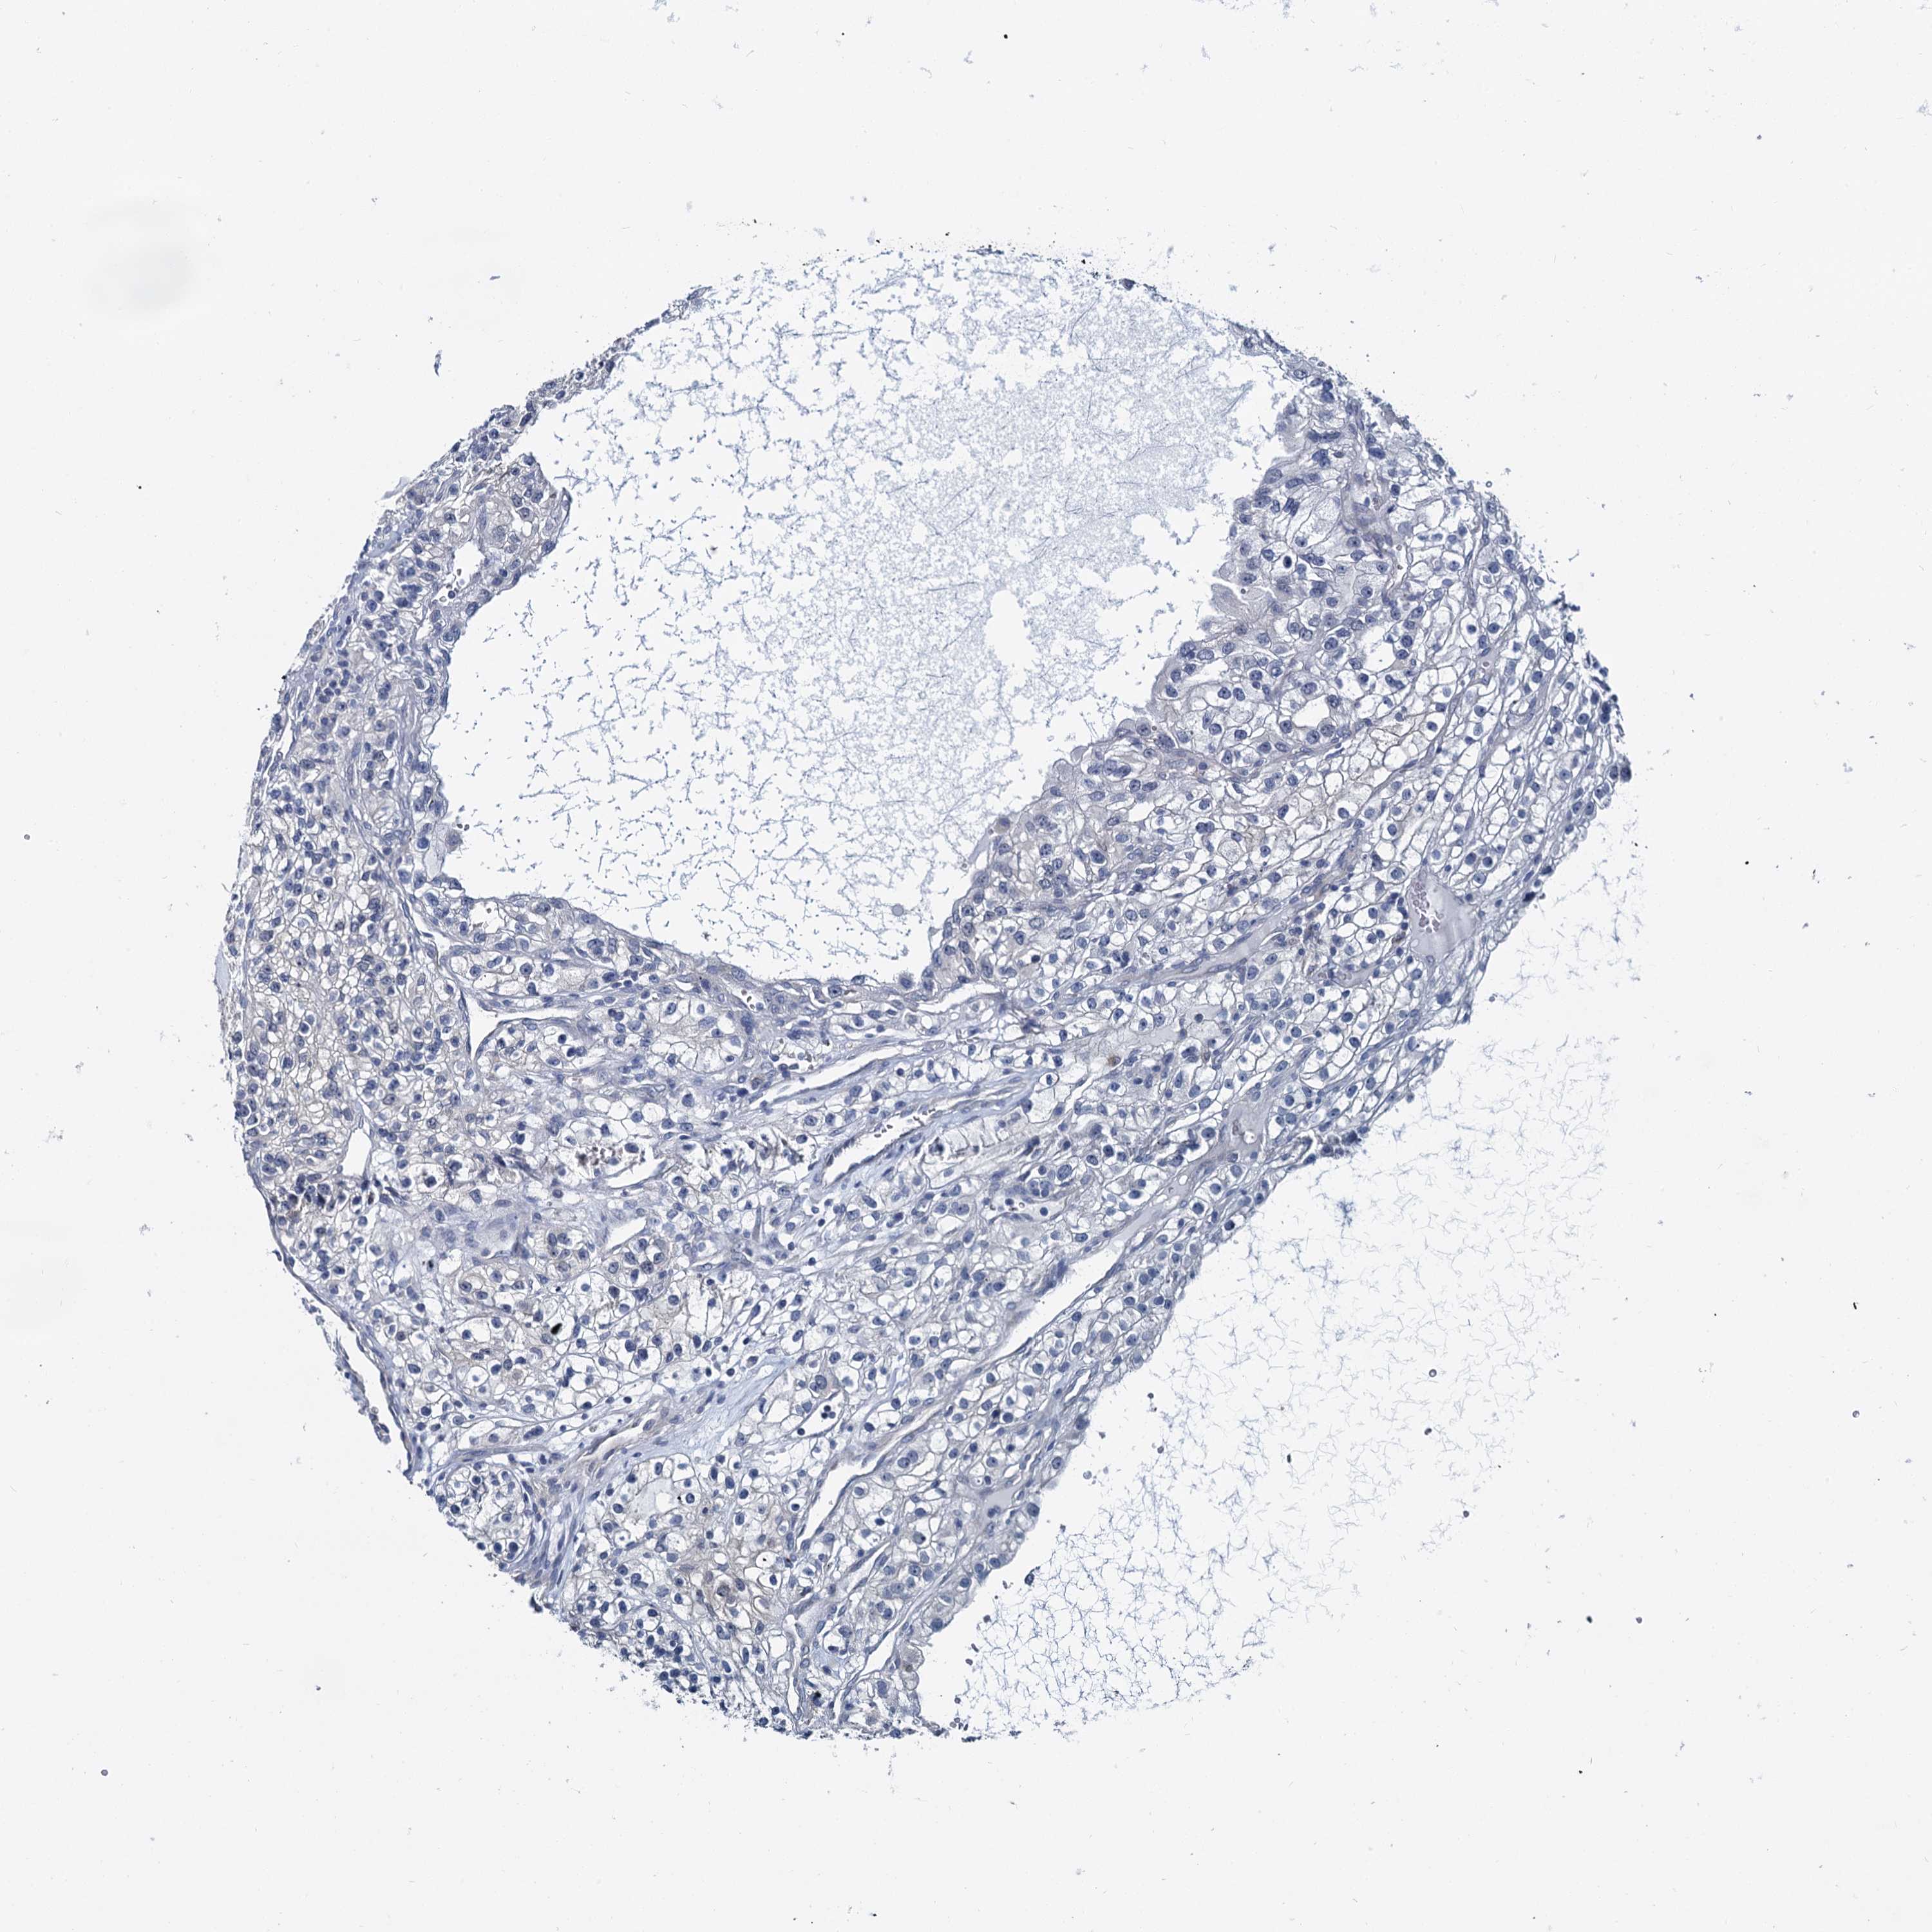

KIDNEY RENAL CLEAR CELL CARCINOMA (TCGA) - Interactive survival scatter ploti

The Survival Scatter plot shows the clinical status (i.e. dead or alive) for all individuals in the patient cohort, based on the same data that underlies the corresponding Kaplan-Meier plots. Patients that are alive at last time for follow-up are shown in blue and patients who have died during the study are shown in red.

The x-axis shows the expression levels (FPKM) of the investigated gene in the tumor tissue at the time of diagnosis. The y-axis shows the follow-up time after diagnosis (years). Both axes are complimented with kernel density curves demonstrating the data density over the axes. The top density plot shows the expression levels (FPKM) distribution among dead (red) and alive patients (blue). The right density plot shows the data density of the survived years of dead patients with high and low expression levels respectively, stratified using the cutoff indicated by the vertical dashed line through the Survival Scatter plot. This cutoff is automatically defined based on the FPKM cutoff that minimizes the p-score. The cutoff can be changed by dragging the vertical line or by entering a cutoff value in the square labeled "Current cut-off".

Under the Survival Scatter plot the p-score landscape (black curve; left axis) is shown together with dead median separation (red curve; right axis). Dead median separation is the difference in median mRNA expression between patients who have died with high and low expression, respectively. It is calculated as follows: median FPKM expression of dead patients with high expression - median FPKM expression of dead patients with low expression. This is intended to aid the user in visually exploring custom cutoffs and the associated p-scores and dead median separation.

Individual patient data is displayed and can be filtered by clicking on one or more of the category buttons on the top of the page. Categories describing expression level and patient information include: high, low, alive, dead, female, male and tumor stages. The scale of the x-axis can be toggled between linear and log-scale by clicking on the "x log" button. Mouse-over function shows TCGA ID, patient information and mRNA expression (FPKM) for each patient.

& Survival analysisi

Kaplan-Meier plots summarize results from analysis of correlation between mRNA expression level and patient survival. Patients were divided based on level of expression into one of the two groups "low" (under cut off) or "high" (over cut off). X-axis shows time for survival (years) and y-axis shows the probability of survival, where 1.0 corresponds to 100 percent.

MIOX is validated prognostic, high expression is favorable in Kidney Renal Clear Cell Carcinoma (TCGA)

: 41.78

Average pTPM 111.2

Number of samples 521